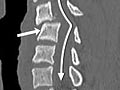

- Find problems of the spine, such as tumors, fractures, deformities, infection, or narrowing of the spinal canal (spinal stenosis).

- Find a herniated disc of the spine.

- Spinal bones (vertebrae) are missing, damaged, or out of alignment.

- One or more discs may be damaged. One or more herniated discs are found.

- The flow of contrast material through the spinal canal is restricted or blocked, which may mean narrowing of the canal (spinal stenosis).

- The vertebrae show signs of arthritis or bone problems caused by osteoporosis.